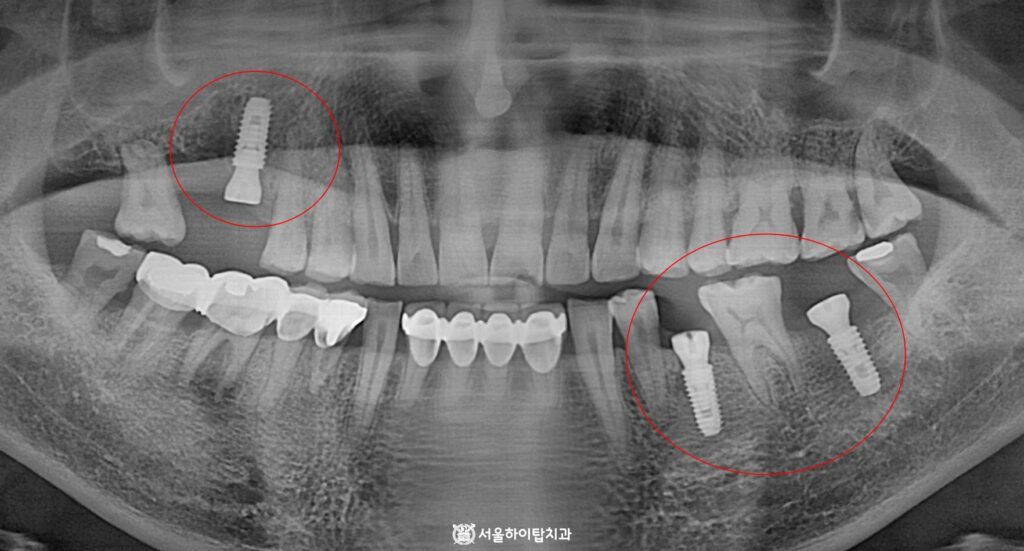

초진

초진 파노라마 엑스레이를 확인해 보면 한눈에 보더라도

상실되고 심하게 훼손된 자연치를 확인할 수 있습니다.

즉, 이는 앞서 부평 치과 에서 말씀드린 골 흡수, 인접치 이동 문제가 나타날 수 있는 소견으로,

실제로 위 사진을 보면, 골 흡수와 사랑니가 점점 기울어지는 모습을 관찰할 수 있습니다.

또한, 반대쪽 어금니는 치근만 남아있는 ‘잔존치근'(Root Rest) 상태로,

저작 활동이 제한되기 때문에 교합 관계가 불안정한 상태임을 알 수 있습니다.